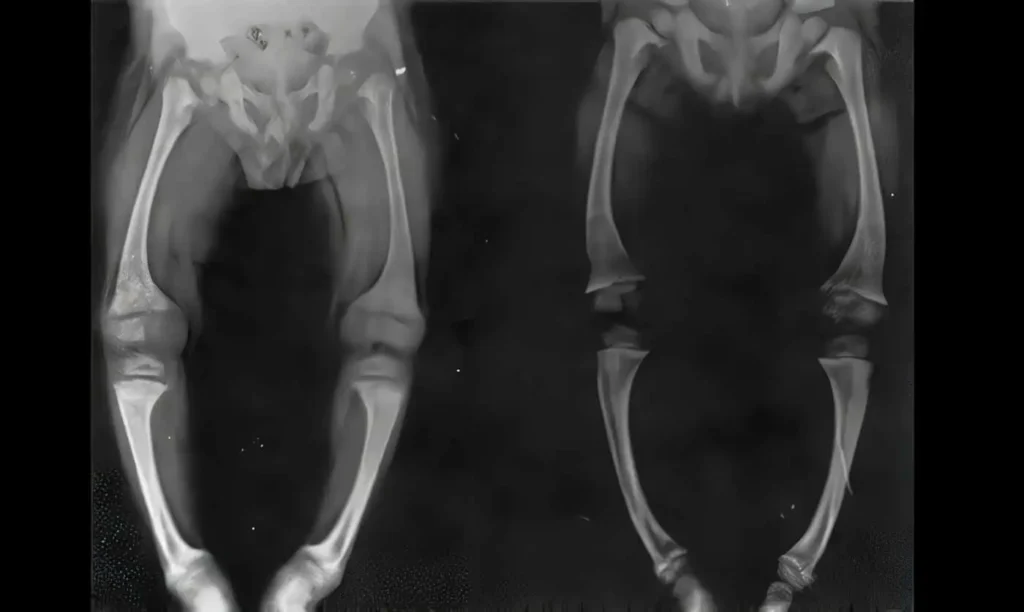

El raquitismo es una manifestación clínica de esta mineralización insuficiente en los niños. La falta de mineralización adecuada en los huesos en crecimiento puede provocar una serie de deformidades esqueléticas. Entre las más comunes se encuentran la curvatura de las piernas, el engrosamiento de los huesos en las muñecas y los tobillos, y el ensanchamiento de la caja torácica. Estas deformidades se deben a la incapacidad de los huesos para resistir las fuerzas mecánicas normales a las que están sometidos durante el crecimiento. La falta de mineralización adecuada también afecta la formación de los cartílagos de las articulaciones, lo que contribuye a la deformación esquelética. Si no se corrige a tiempo, el raquitismo puede provocar secuelas permanentes en el esqueleto, como la deformación de la columna vertebral o la discapacidad en la marcha.

Uno de los hallazgos más característicos en el raquitismo es la hipertrofia de los condrocitos en las placas de crecimiento, lo que provoca engrosamientos bulbosos en las articulaciones, particularmente en las rodillas y los tobillos, que a menudo se presentan con piernas arqueadas (genu varum) o con las rodillas hacia adentro (genu valgo). Además, el engrosamiento de las articulaciones costocondrales produce lo que se conoce como el «rosario raquítico», una deformidad visible en la zona donde las costillas se unen al esternón. En muchos casos, los pacientes con raquitismo también desarrollan curvaturas anormales de la columna vertebral, como la cifosis o la lordosis lumbar, lo que agrava aún más las alteraciones esqueléticas.